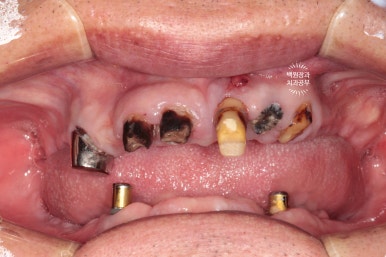

그런데 위 앞니 보철물이 이차충치로 인해 떨어져 나가게 되면서 보니 충치가 심해서 뿌리만 남았더라구요..

보시다시피 상태가 좀 심각했습니다.

그리고 왼쪽 사진을 보시면, 회색의 무언가가 보이실텐데...

잇몸뼈 안에 있어야할 임플란트가 주변의 뼈가 녹아 없어지면서 드러나 있는 상태였어요.

위턱을 보시면 정말로 뿌리만 있는 치아를 보실 수 있어요.

다만, 남은 잇몸뼈들은 상대적으로 건전하여 틀니를 하기에는 무리가 없어 보였습니다.

아래는 임플란트 2개를 이용한 임플란트 틀니 (=오버덴쳐)를 사용중이셨는데요,

왼쪽 임플란트는 이미 잇몸 밖으로 임플란트의 일부가 드러나 있었어요.

임플란트 주위염이라고 부르는데요~ 상태가 심각하여 제거해야하는 수준이었습니다.

비교적 오른쪽 임플란트는 낫군요..